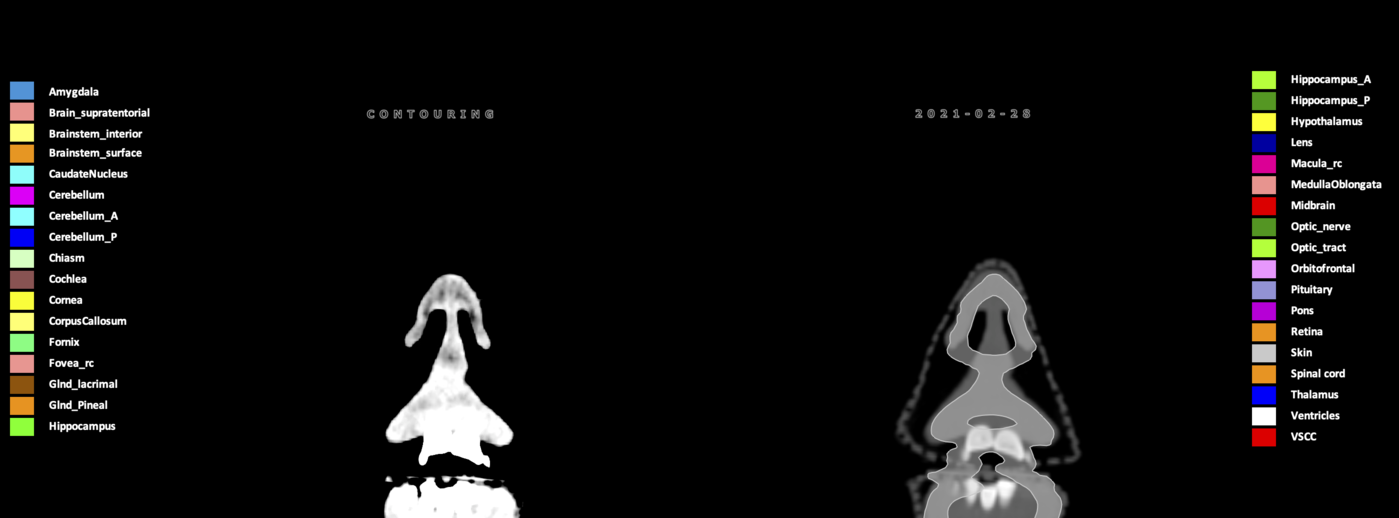

Included are all OARs known to be relevant for radiation-induced toxicity in neuro-oncology: brain, brainstem (midbrain, pons, medulla oblongata), chiasm, cerebellum (anterior & posterior), cochlea, cornea, hippocampus (anterior & posterior), hypothalamus, lens, lacrimal gland, optic nerve, pituitary, skin, and vestibular & semicircular canals. To further facilitate research on cognition, vision and radiological changes after irradiation of the brain, potential clinically-relevant OARs are included: amygdala, caudate nucleus, cerebellum (anterior & posterior), corpus callosum, fornix, macula, optic tract, orbitofrontal cortex, periventricular space (PVS), pineal gland, and thalamus.

Three-dimensional delineation of the 25 consensus OARs for neuro-oncology are shown on CT (WW/WL 120/40, 3000/600), 3T MR images, (T1Gd, T2FLAIR 1mm) and 7T MR (MP2RAGE 0.7 mm). All are presented in transversal, sagittal and coronal view.